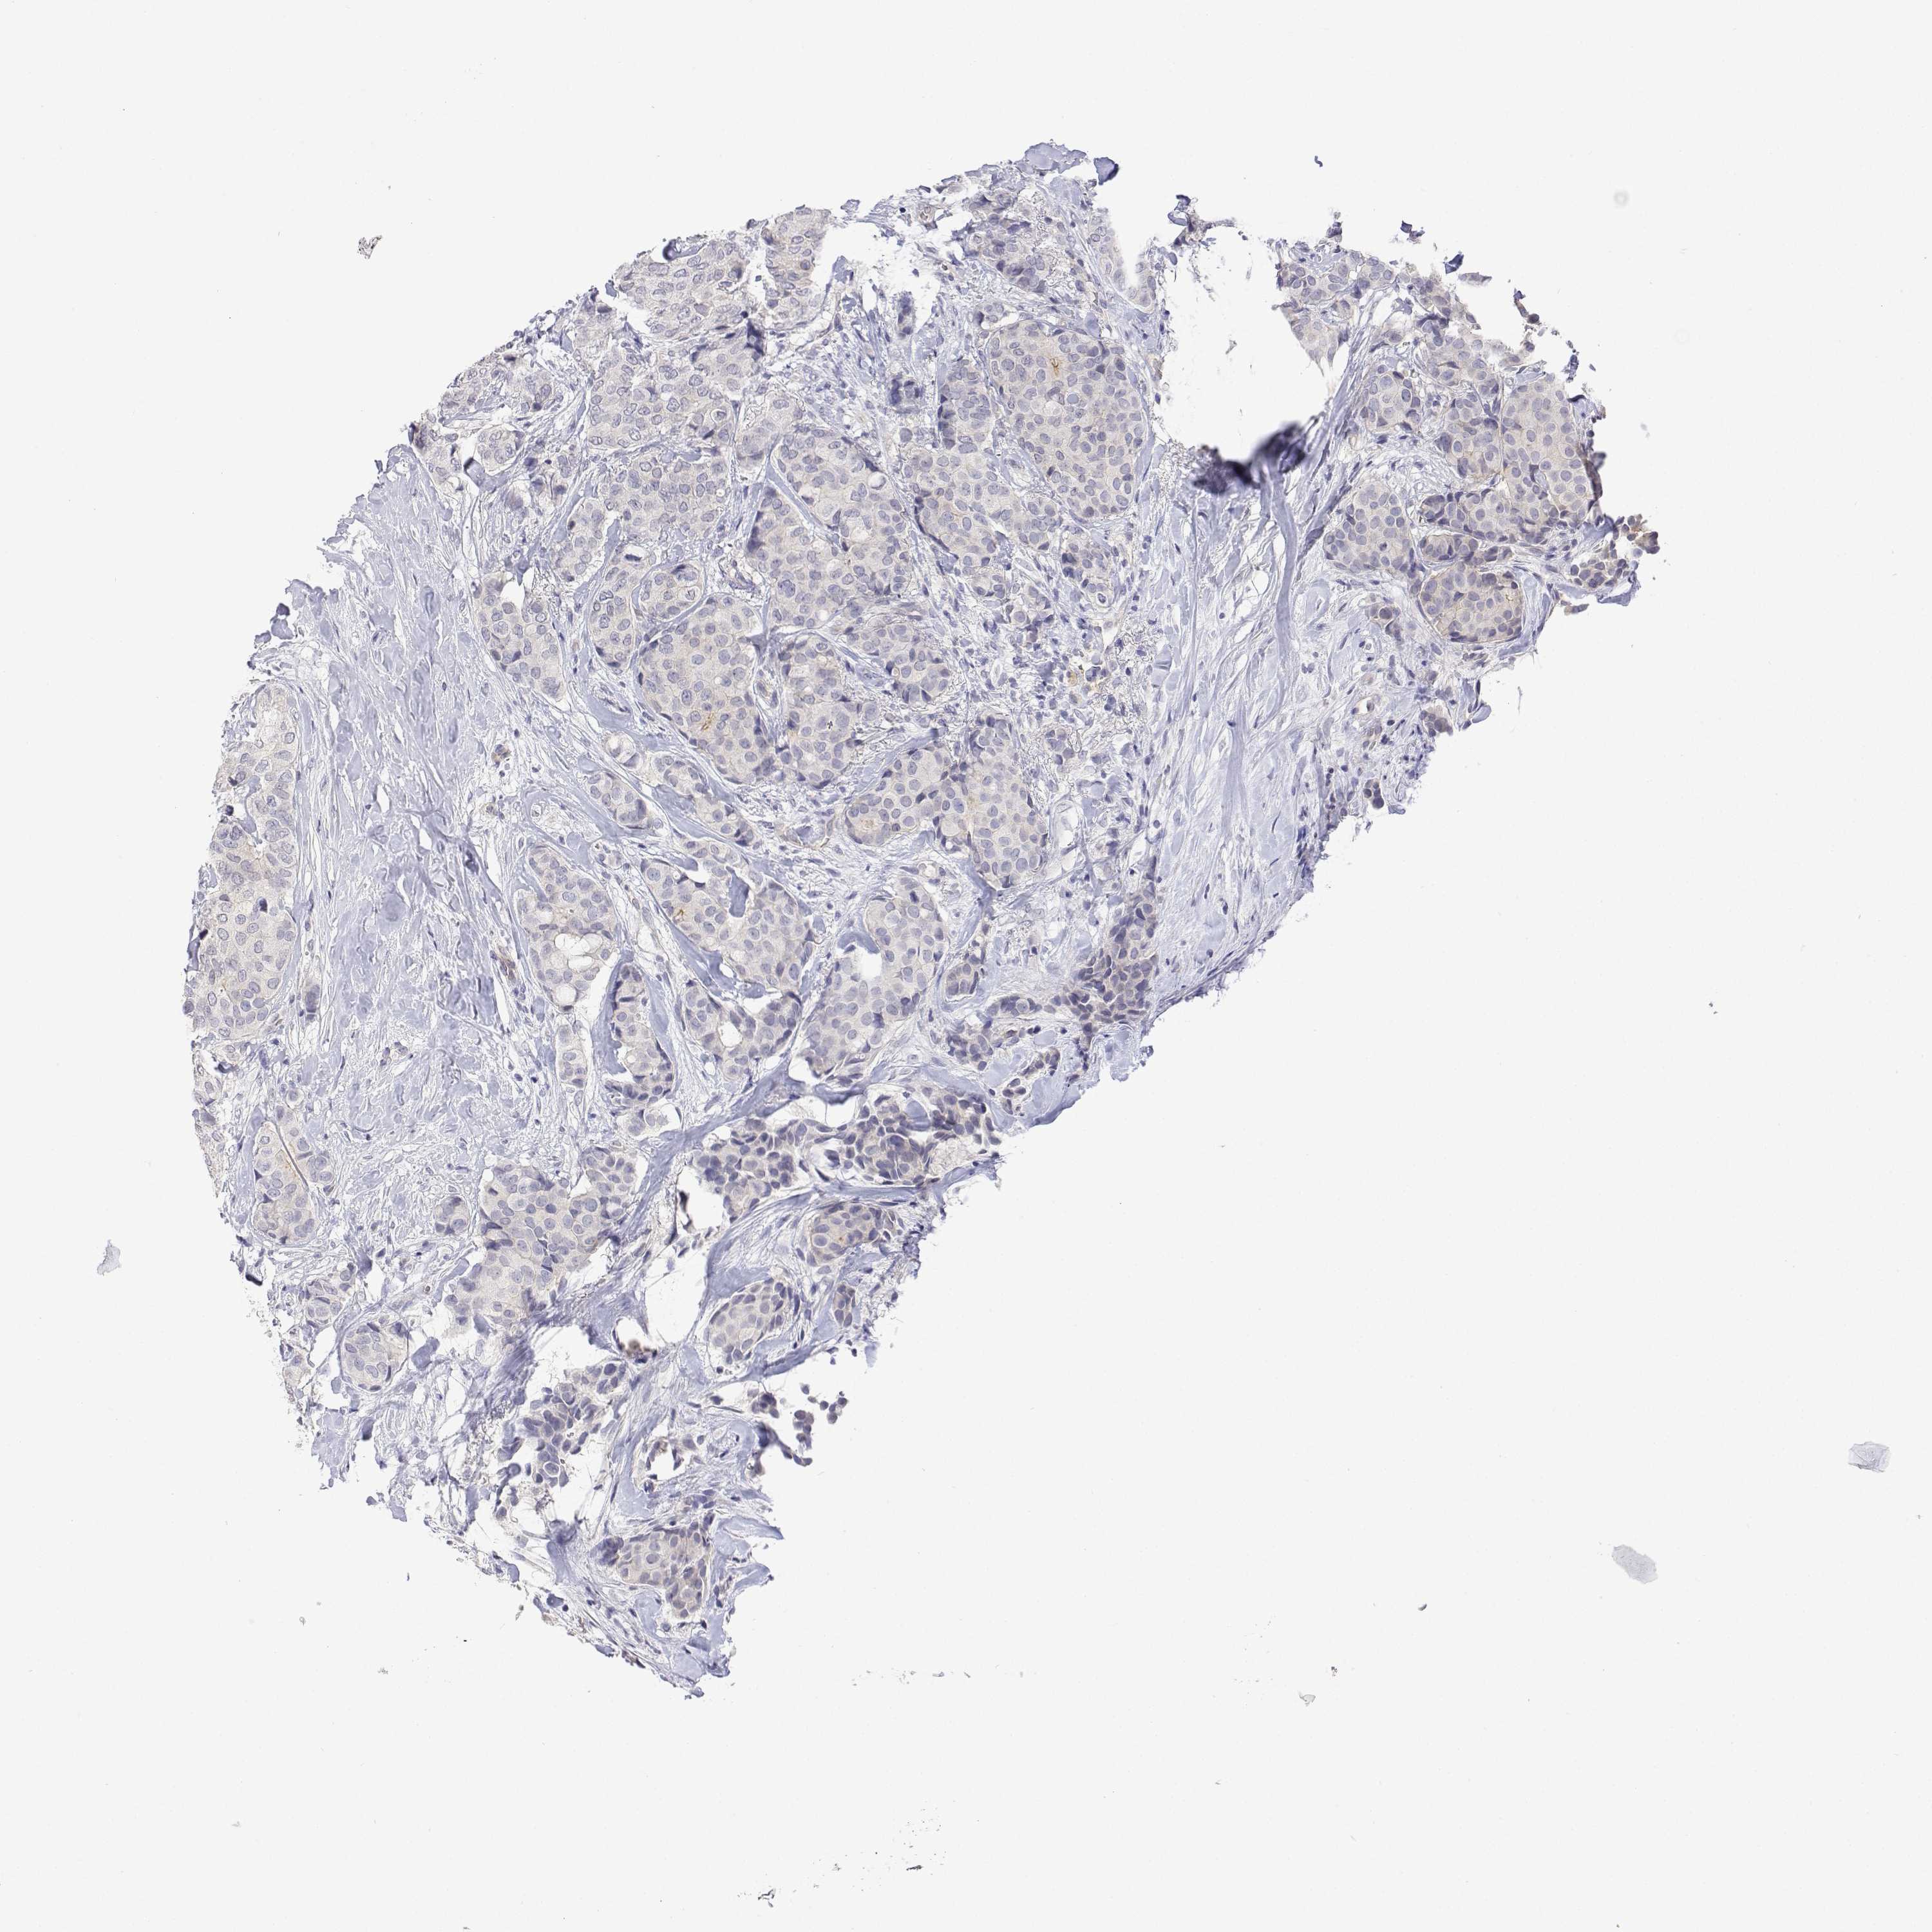

BRCA TCGA BRCA VALIDATION PROTEIN EXPRESSION